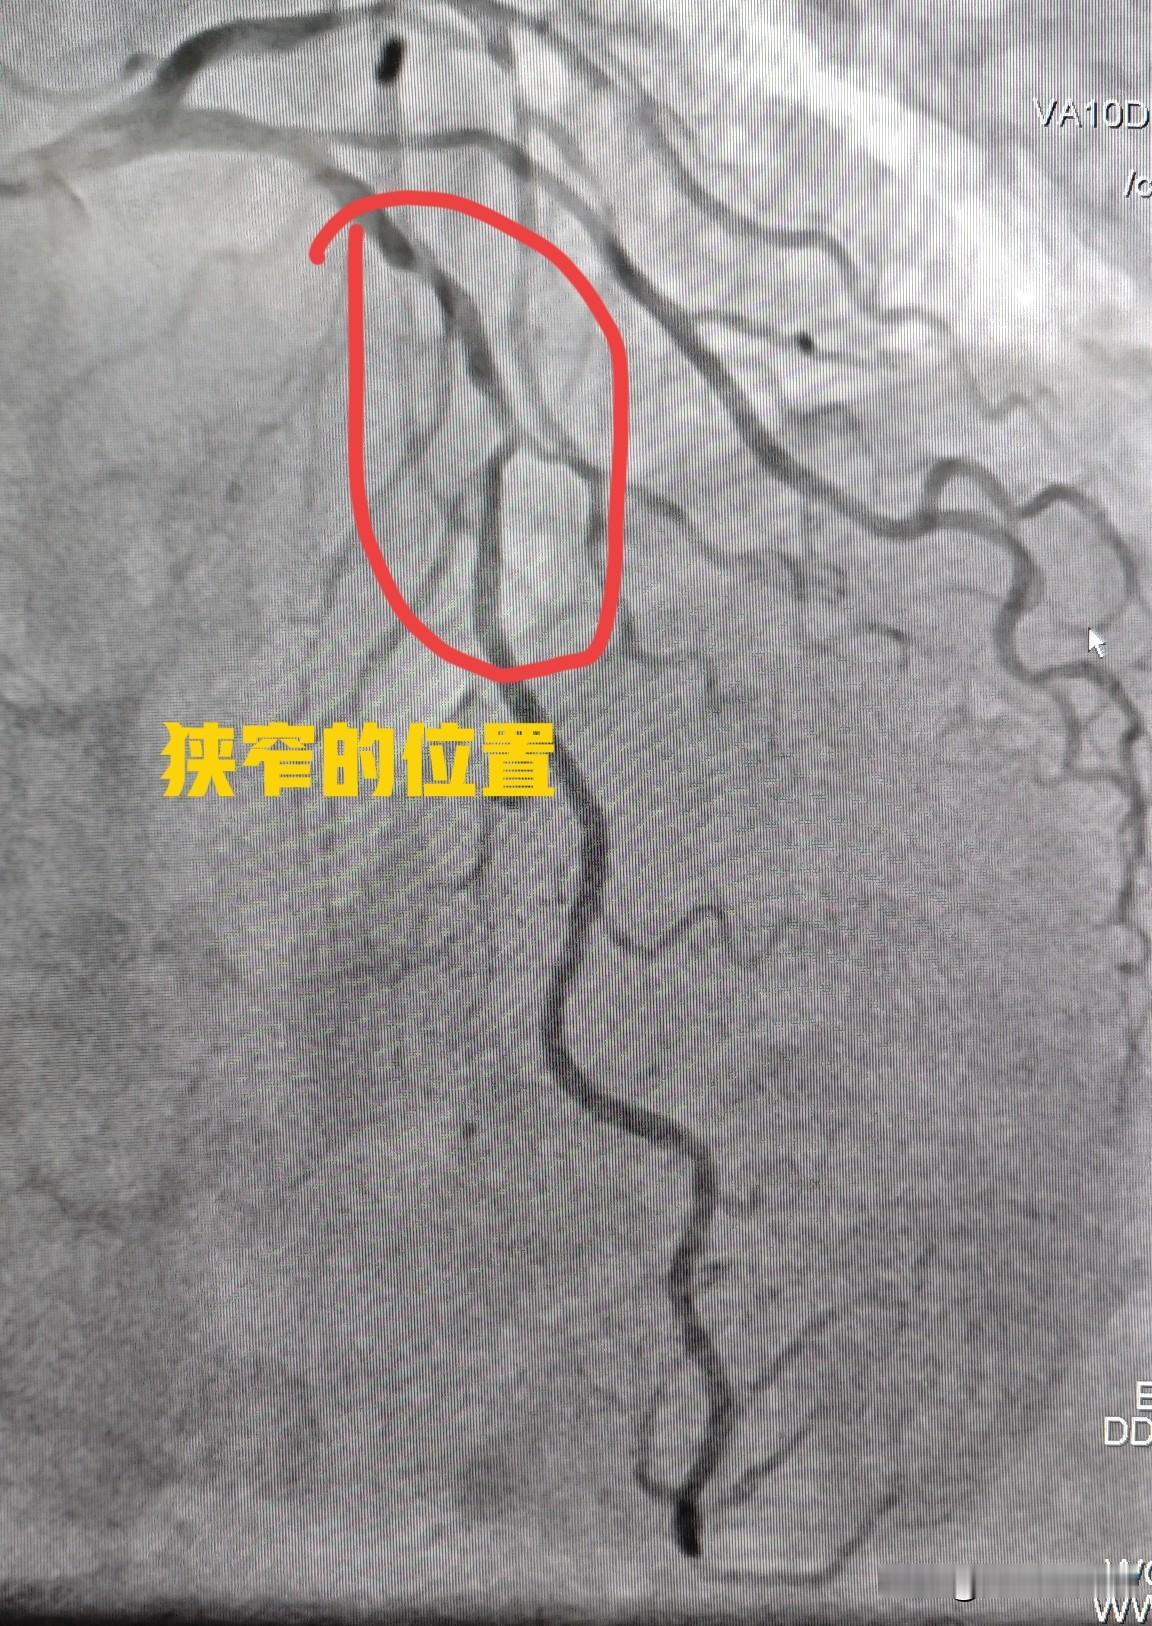

78 岁老人冠心病药物保守治疗。今天给一个78岁老年女性的冠心病患者做了心脏造影

高龄女性,多根血管狭窄,耐受性差,低体重,分次手术更安全。75 岁女性患者,三支

82 岁老人做冠脉支架,风险还是高一些。82 岁男性,频繁发作胸痛,做了冠状动脉